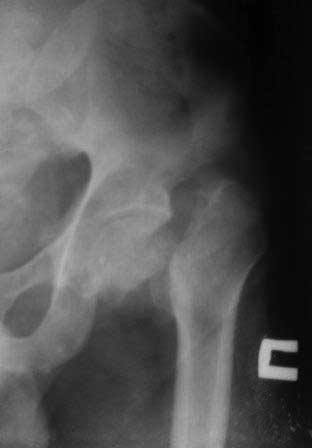

Здравствуйте, уважаемые коллеги!Больной 1976г.р. получил тяжелую сочетанную травму в апреле ,был в коме около 1 месяца. 09.05.12г.операция КДО аппаратом Илизарова в другом регионе,перелом шейки бедра пропущен. Обратился к нам сегодня для дальнейшего лечения, ходит c двумя костылями, укорочение 4см, на правой голени аппарат Илизарова в вальгусном положении, разболтанность в пр.т/б суставе,повреждение ипсилатеральное. В плане сначала БИОС б/берцовой кости после остеотомии м/берцовой и коррекции деформаций голени,после т/эндопротезирование пр. т/б сустава, Нужен совет: 1.последовательность операции? 2.или другие варианты лечения? С уважением Абдурашид. р-снимки прилагаются-от 17.12.12г.

Как-то я пропустил это сообщение, прошу прощения. В этом случае, полагаю, эндопротезирование будет лучшим вариантом. Межвертельная вальгизирующая остеотомия тут вряд ли имеет много шансов на успех.

|